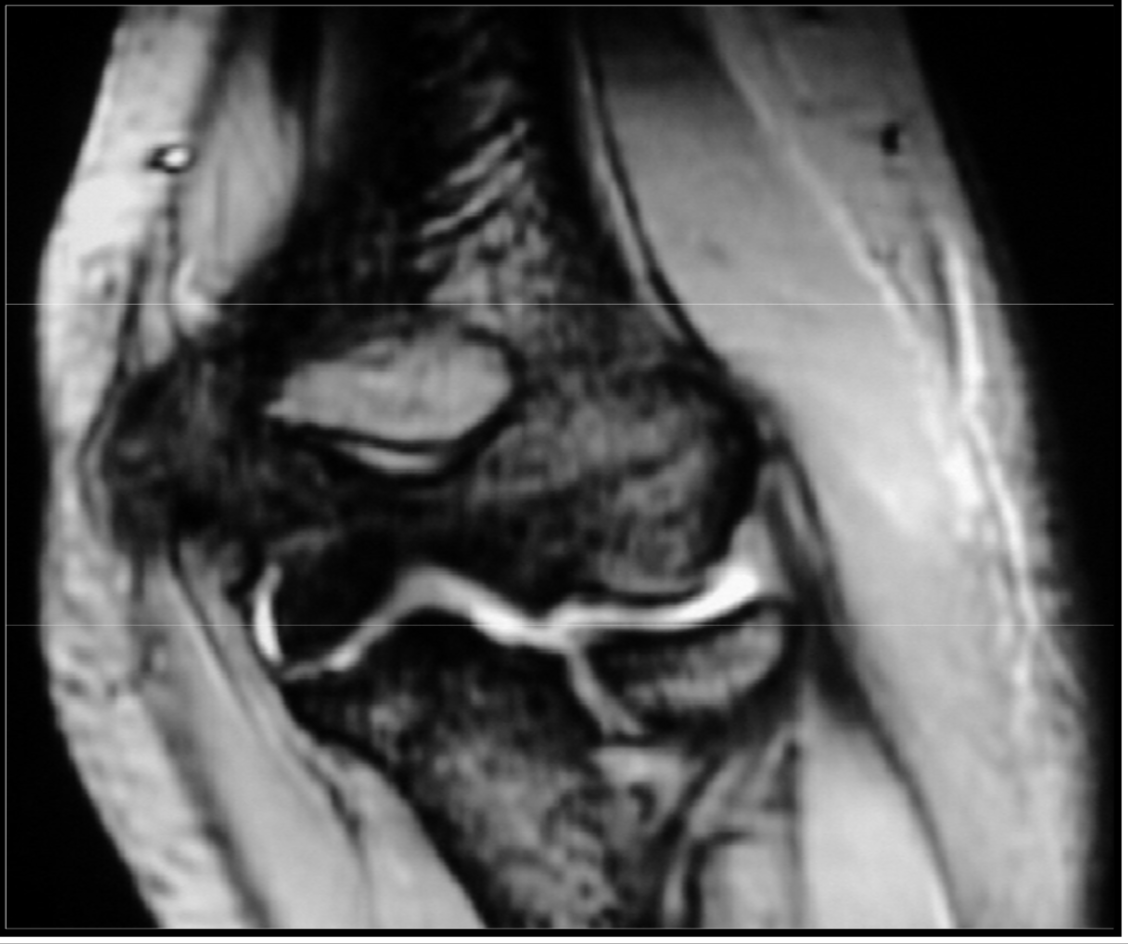

Synovial herniation pit or Pitt’s pit

variation anat normal